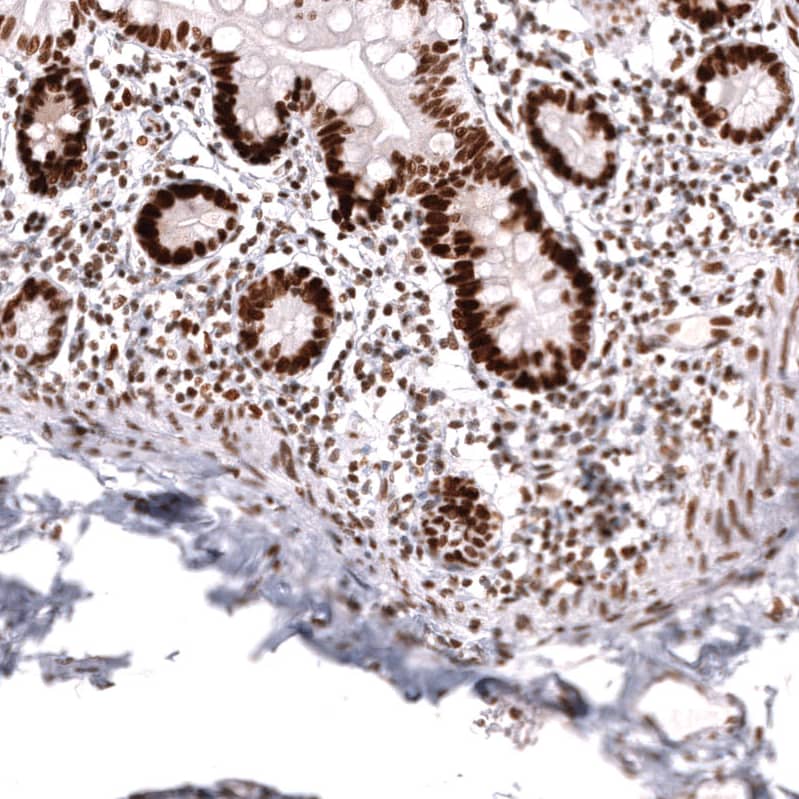

Immunohistochemistry-Paraffin: MSH2 Antibody (CL13724) [NBP3-24573]

Staining of human small intestine shows strong nuclear positivity in glandular cells.